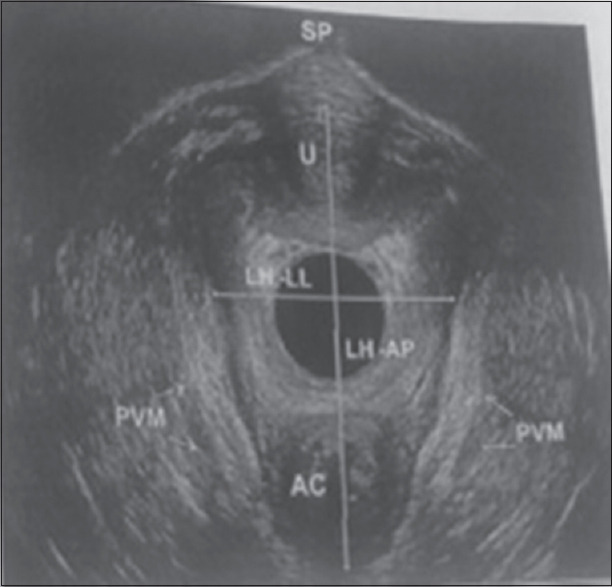

Materials and methods: It is a prospective study conducted over 40 women of SUI by endovaginal ultrasound on rest and Valsalva preoperatively and 6 months postoperatively for levator hiatus (LH), pubovisceral thickness, urethral length, and bladder neck (BN) position. A 24 h pad test was also performed on all women at the same time for grading of SUI. Treatment given was medical in 4 (10%), Burch colposuspension in 18 (45%), and tension-free obturator tape in 18 (45%).

Results: The mean age, parity, and body mass index in the study were 41.60 years, 2.73, and 24.2 kg/m2, respectively. All 40 (100%) patients had SUI with a mean duration of symptoms being 4.04 years. On 24 h pad test, mild SUI was in 4 (10%), moderate SUI in 33 (82.5%), and severe SUI in 3 (7.5%) with mean preoperative 24 h pad test being 36.69 g which significantly reduced to 9.79 g postoperatively (P = 0.001). There was significant change in LH and pubovisceral thickness with treatment of SUI. Overall urethral length increased but there was significant decrease in urethral length on Valsalva after the treatment (0.40 cm vs. 0.28 cm, P = 0.04) and significant reduction in BN descent after Valsalva after treatment (0.41 cm vs. 0.27 cm, P = 0.001).